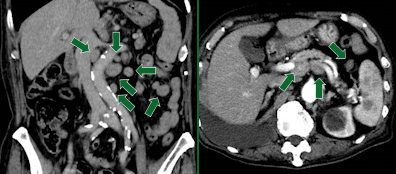

リンパ腫腫大:首や脇、足の付け根などのリンパ節の多いところに腫れやしこりを触知します。

悪性リンパ腫は白血球のリンパ球ががん化する病気ですが、リンパ節が腫大する原因は多々あり、ウイルスや細菌感染による炎症などが挙げられます。

画像の症例はリュウマチ治療中に腹部エコー検査にて膵臓嚢胞が疑われ、CT造影検査となった症例です。

結果として、矢印の多発的なリンパ節腫大が確認されましたが、リュウマチのお薬を中止したことにより、リンパ節の腫大は消失しました。

CT検査は治療中の薬の効果判定、副作用の確認にも有用です。